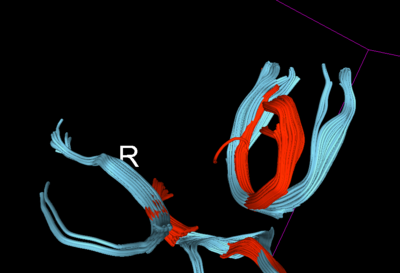

Therefore, for further validation of the improvement post-QC, we created some fiducials along the corpus callosum and used the same fiducials for tractography in DTI before and after QC. Considerable improvement (in terms of what is an expected tract geometry) was seen specially in the fibers of the QCed Acute DTI scan.

For a longitudinal evaluation, its necessary to have all the DTI scans co-registered. Using the QCed versions, we co-registered the acute and chronic timepoints using the corresponding FA images, with the chronic FA image as our moving image. We also applied masks to improve the registration accuracy. The obtained affine + spline transform was applied to the DTI image along with tensor-appropriate resampling. Following the co-registration, a common ROI was created for the middle portion of the corpus callosum tract which for the given patient, seems to be in the region not directly in the proximity of the lesions. The fibers from the chronic timepoint seems to have undergone some geometry changes as well as the associated diffusion profiles indicate a loss of white matter integrity over time.